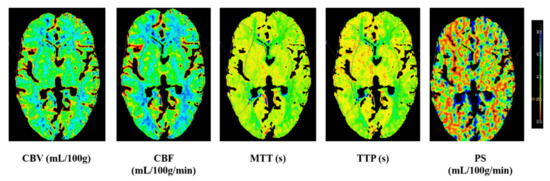

| CT perfusion parameters | |

| rCBV | 1.0 (0.94–1.03) |

| rCBF | 1.11 (0.97–1.31) |

| rMTT | 0.88 (0.75–1.01) |

| rTTP | 0.97 (0.92–1.0) |

| rPS | 1.01 (0.90–1.05) |